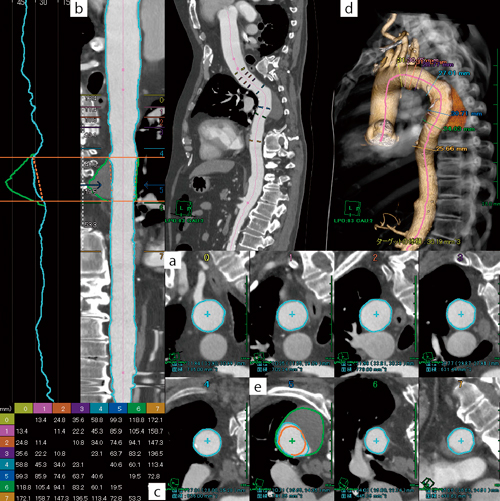

本ソフトウェアでは,上記の過程で作成された血管軸を基に,血管内径の自動抽出を行い,複数箇所の最大径,最小径,平均直径を同時に計算,表示することが可能である(図2 a)。また,閾値の設定や抽出方法の変更により,外径に近い計測を行ったり,石灰化を省きながら内径を計測したりする細かな計測が可能なのも特長である。加えて,平均直径はグラフ(トレンドグラフ)にて表示が可能で,血管径の変化を連続的に検討することができる(図2 b)。Cross sectional imageは,ストレートCPR上で指定した任意の6点での表示が可能で,血管径や血管壁の詳細な評価が可能である。また,指定した6点においては血管軸方向の距離の任意の組み合わせを別表にてリアルタイムに表示しており(図2 c,d),治療計画において測定すべき血管軸上の距離を容易に網羅できる。

●血管解析に最適化した自動マスク作成

図2 胸部下行大動脈瘤における血管解析画面

a:cross sectional image

b:ストレッチCPRと内径(水色),外径(緑色)のグラフ

c:指定された6点間の組み合わせ距離

d:3D volume rendering(VR)(骨および壁在血栓表示)

e:外径認識部分のcross sectional image(緑線)